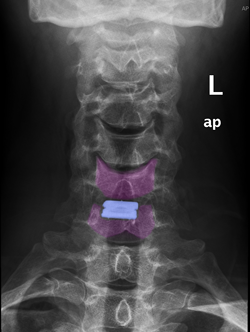

Πρόσθια αυχενική δισκεκτομή και τοποθέτηση τεχνητού αυχενικού δίσκου (μπλέ) Α6-Α7. |